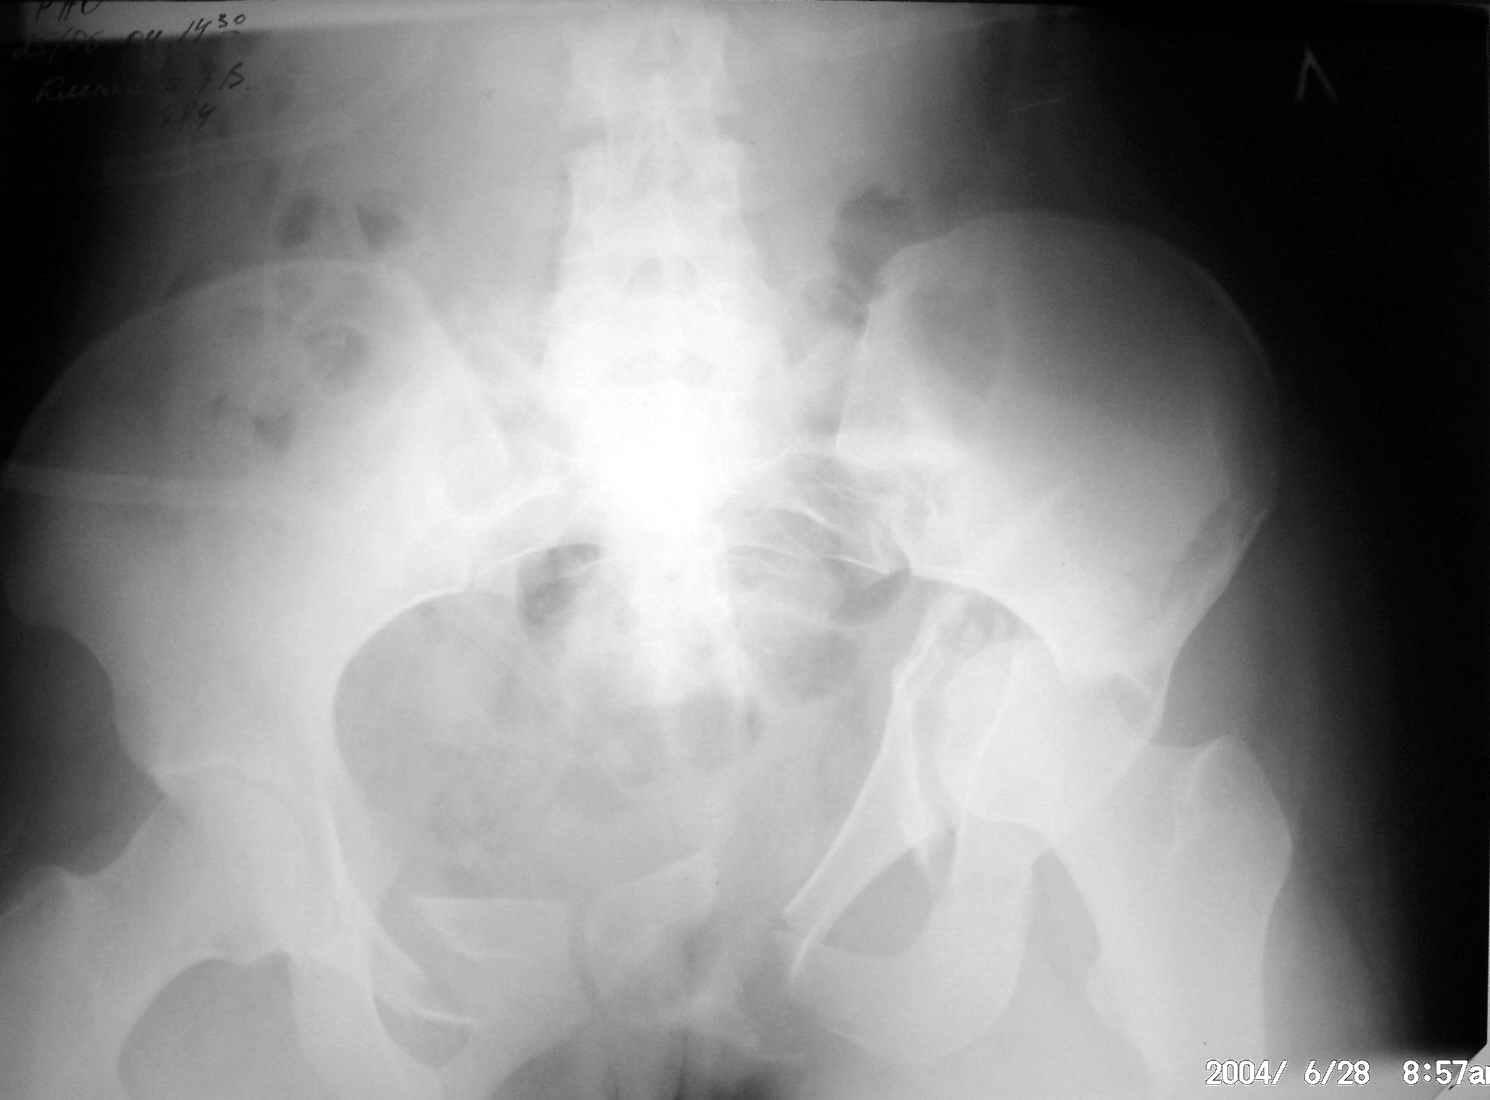

Дорогие коллеги,Посоветуйте, как лучше лечить пациентку с травмой таза после автоаварии? Пока нходится на вытяжении за обе ноги.В.П.Охлопков,Новоуральск.

Повреждение сложное. DS:Ротационно нестабильное повреждение таза, перелом боковой массы крестца,ипсилатеральный высокий двухколонный перелом вертлужной впадины с центральным смещением сустава, двусторонний перелом лонных и седалищных костей.

При оперативном лечении прогноз относительно благоприятный. Показано два доступа - чрезвертельный Y-образный и затем синтез лонных костей двумя пластинами.

Запасной вариант вместо второго доступа - передняя рама аппарата, но он не гарантирует хорошую анатомию.

Консервативное лечение бесперспективно с точки зрения дальнейшего качества жизни.

Перед операцией необходимо скелетное вытяжение по оси бедра 10-12 кг.

Вытяжение за вертл не только бессмысленно, но и опасно. Гамак не нужен.

Больная должна быть в состоянии перенести 4-6 часовую операцию и литровую кровопотерю, быть без пролежней.